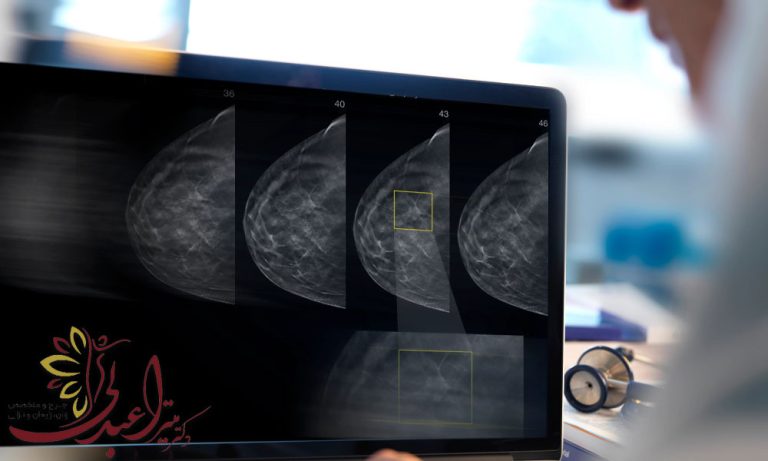

ماموگرافی با چه هدفی انجام می شود؟

ماموگرافی با چه هدفی انجام می شود؟ ماموگرافی یکی از روش های مهم و مؤثر در تشخیص و پیشگیری از بیماری های پستان، به ویژه سرطان، است. این روش تصویربرداری با استفاده از اشعه ایکس، باعث می شود تغییرات غیرطبیعی در بافت پستان را قابل مشاهده شوند و به پزشکان